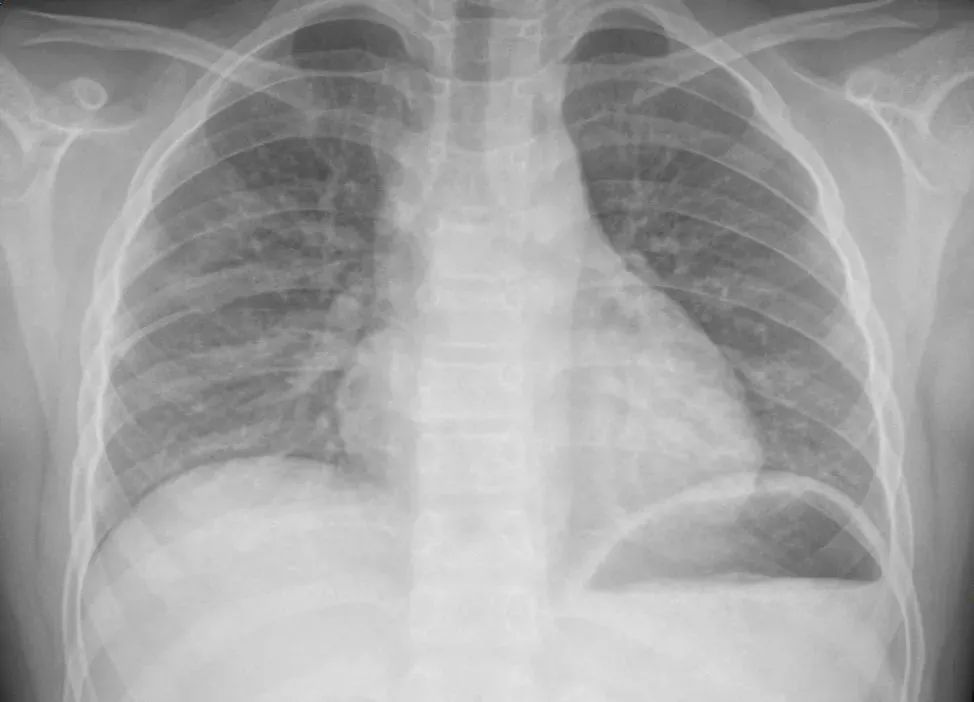

▲图/央视新闻

就在本月,杭州市儿童医院呼吸内科转入了两位特殊的小病人——两位小朋友在家里发现了妈妈的防晒喷雾,俩人就在房间里玩了起来,相互对喷了半小时,120ml的防晒喷雾一下子用掉了半瓶。

▲图/杭州市儿童医院

结果,不久两个孩子都出现了阵发性刺激性干咳,还出现了头痛、呕吐,家人赶紧送到医院就诊,胸片检查显示,有肺炎征象,医生及时给予治疗。